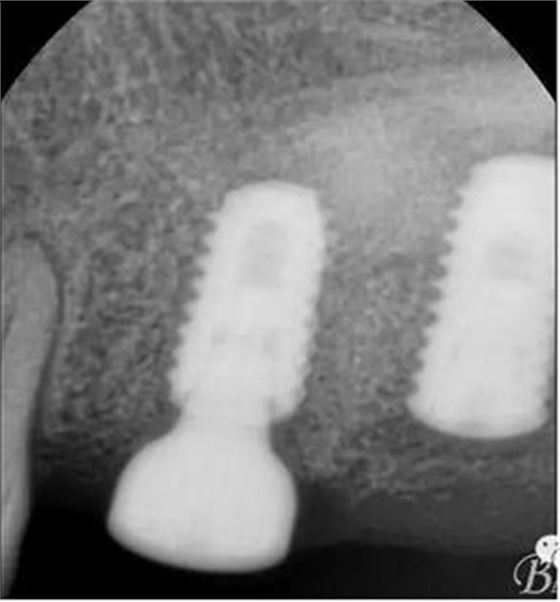

術后x光片,右上6直接上愈合基臺,但未完全就位,右下7手術過程略

這是術后1月的片子,重新就位愈合基臺